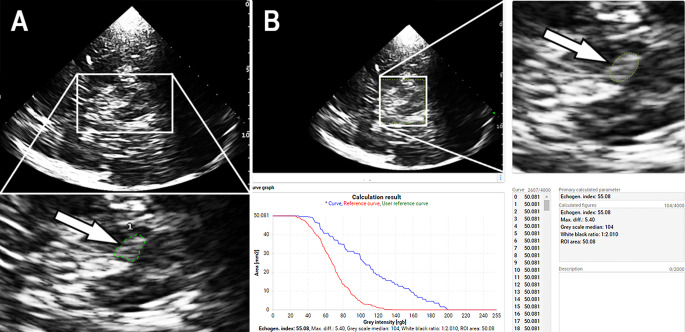

Quantitative susceptibility mapping (QSM) and transcranial sonography (TCS) offer proximal evaluations of iron load in the substantia nigra. Our prospective study aimed to investigate the relationship between QSM and TCS measurements of nigral iron content in patients with Parkinson's disease (PD). In secondary analyses, we wanted to explore the correlation of substantia nigra imaging data with clinical and laboratory findings. Eighteen magnetic resonance imaging and TCS examinations were performed in 15 PD patients at various disease stages. Susceptibility measures of substantia nigra were calculated from referenced QSM maps. Echogenicity of substantia nigra on TCS was measured planimetrically (echogenic area) and by digitized analysis (echo-intensity). Iron-related blood serum parameters were measured. Clinical assessments included the Unified PD Rating Scale and non-motor symptom scales. Substantia nigra susceptibility correlated with echogenic area (Pearson correlation, r = 0.53, p = 0.001) and echo-intensity (r = 0.78, p < 0.001). Individual asymmetry indices correlated between susceptibility and echogenic area measurements (r = 0.50, p = 0.042) and, more clearly, between susceptibility and echo-intensity measurements (r = 0.85, p < 0.001). Substantia nigra susceptibility (individual mean of bilateral measurements) correlated with serum transferrin saturation (Spearman test, r = 0.78, p < 0.001) and, by trend, with serum iron (r = 0.69, p = 0.004). Nigral echogenicity was not clearly related to serum values associated with iron metabolism. Susceptibility and echogenicity measurements were unrelated to PD duration, motor subtype, and severity of motor and non-motor symptoms. The present results support the assumption that iron accumulation is involved in the increase of nigral echogenicity in PD. Nigral echo-intensity probably reflects ferritin-bound iron, e.g. stored in microglia.